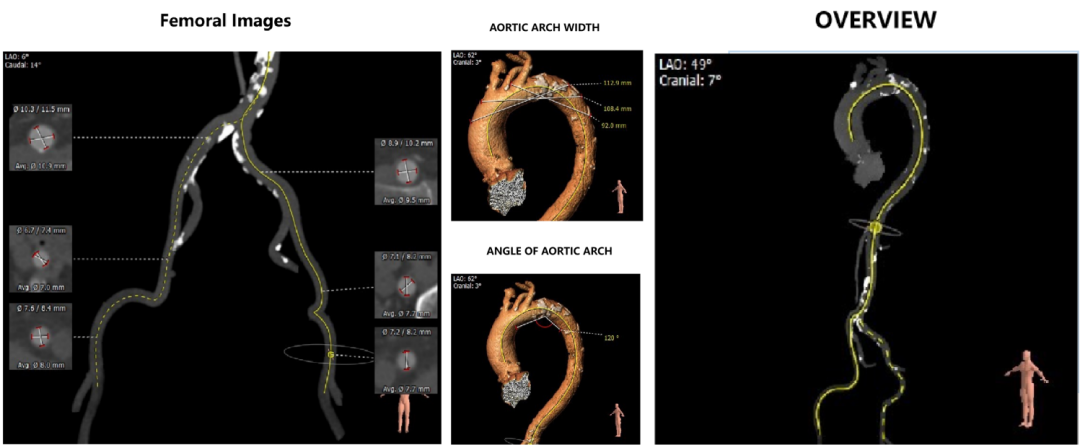

外周血管及主动脉弓解剖

入路血管钙化明显,双侧血管内径良好,整体入路血管条件尚可。

3、入路血管见多发钙化,双侧血管内径良好,整体入路血管条件尚可。